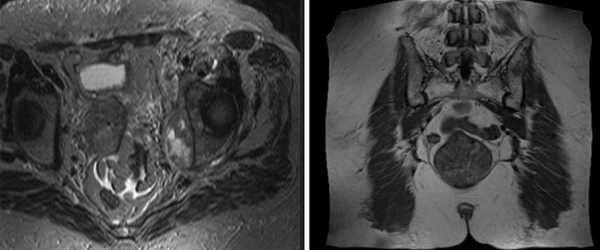

МРТ-признаки остеомиелита лонных костей: расширение сочленения и скопление жидкости с формированием параартикулярных затеков (длинные стрелки), разрастание грануляционной ткани (короткие стрелки), Т2-ВИ, аксиальная (а) и коронарная (в) плоскости

МРТ костей таза показывает множественные очаги, что говорит о метастатическом поражении